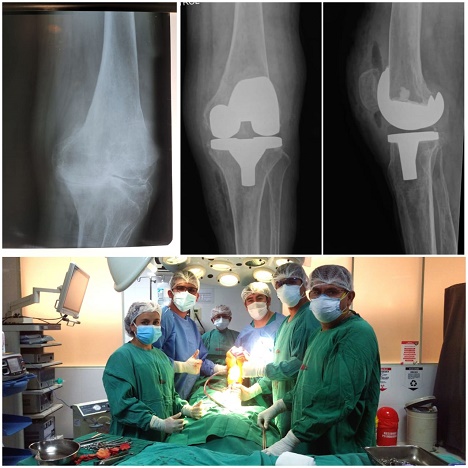

Dr. Elberth Tafur Sarmiento

Soy médico especialista en Traumatología y Ortopedia con más de 10 años de experiencia en el diagnóstico y tratamiento traumatológico. He obtenido una mejoría del 90% de mis pacientes, quienes le han dado un nuevo rumbo a su vida. Trabajo con dedicación, responsabilidad y mucha empatía para comprender a quienes solicitan mi ayuda.

Deseo replicar los resultados en el departamento de Traumatología del Hospital Regional de Cajamarca, Entidad actual de trabajo.